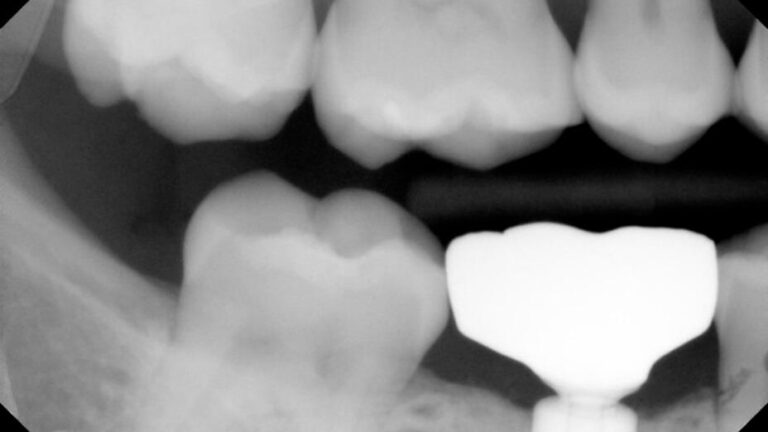

The patient was referred by Dr. W. for retrieval of a fractured abutment from an Ankylos CX implant in the #30 site.